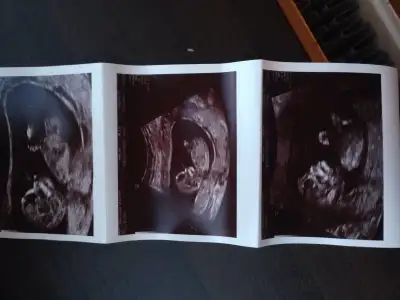

HosgeldinizMerhabalar bende yeni üye oldum ve bebeğimin cinsiyetini çok merak ediyorum yardımcı olursanız sevinirim.

Cinsiyetini bende cok merak ettim hemde cok hatta cin takvimi uzmani oldum acaba surekli yanlismi bakıyorum diye yaklasik 50 kadinin üzerinde denedim ama kendimdede o kadinlarin hicbirindede yanilmadim bi iznillah istersen seninkinede bakalim